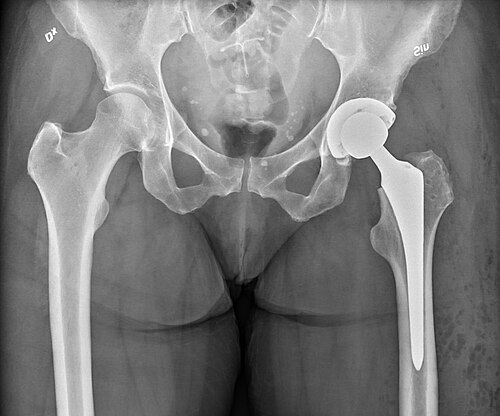

Total hip replacement

Mikael Häggström, M.D. Author info - Reusing images- Conflicts of interest:  Non · CC0 · source

Total hip replacement is a surgical procedure in which a diseased or damaged hip joint is replaced with prosthetic components to relieve pain and restore function. It is commonly performed for advanced degenerative joint diseases, traumatic injury, and certain congenital or inflammatory conditions. Outcomes depend on patient selection, surgical technique, implant design, and rehabilitation.

Prosthesis types and materials

Prostheses differ by fixation method (cemented, uncemented, or hybrid), bearing surfaces (metal-on-polyethylene, ceramic-on-ceramic, ceramic-on-polyethylene), and modularity concepts advanced by implant manufacturers and biomedical researchers. Materials are selected based on biocompatibility studies from institutes and governmental regulatory agencies, and include cobalt-chromium alloys, titanium alloys, polyethylene formulations, and alumina or zirconia ceramics. Design evolution has been influenced by contributions from pioneering surgeons and biomedical engineers affiliated with academic centers and research institutions.